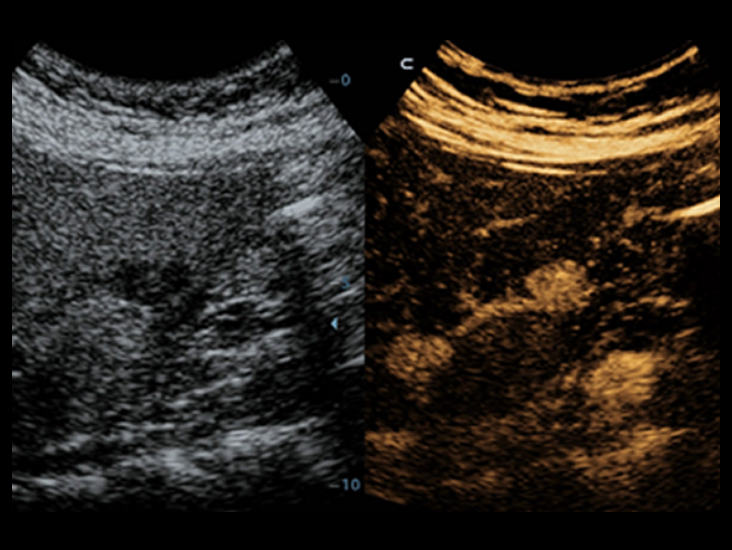

Familia de transductores optimizados: amplia gama de cobertura de aplicaciones

Gracias a una versĂĄtil combinaciĂłn de transductores, el DC-40 con Full HD ofrece el rendimiento mĂĄs eficiente en una amplia gama de aplicaciones. AdemĂĄs, proporciona una calidad avanzada de imĂĄgenes en una gran variedad de tipos de pacientes.

Transductores ComboWave

En comparaciĂłn con los sensores tradicionales, los transductores ComboWave utilizan un nuevo tipo de material piezoelĂ©ctrico compuesto que optimiza notablemente el espectro acĂșstico y reduce la impedancia acĂșstica. AdemĂĄs de integrarse con la tecnologĂa Ășnica 3T de Mindray, los transductores lineales ComboWave ofrecen un rendimiento sobresaliente con una gran uniformidad y resoluciĂłn de imagen en ecografĂas vasculares, de tiroides, de mama, etc.